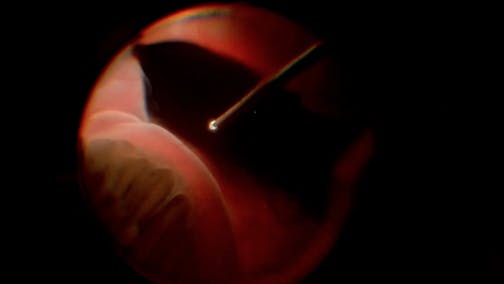

Optic Nerve Pit

Kourous A. Rezaei, MD